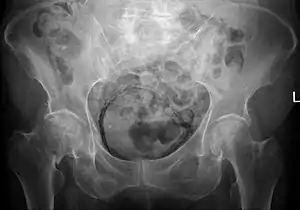

![]() | |

| Regulation of urine production by ADH and aldosterone | |